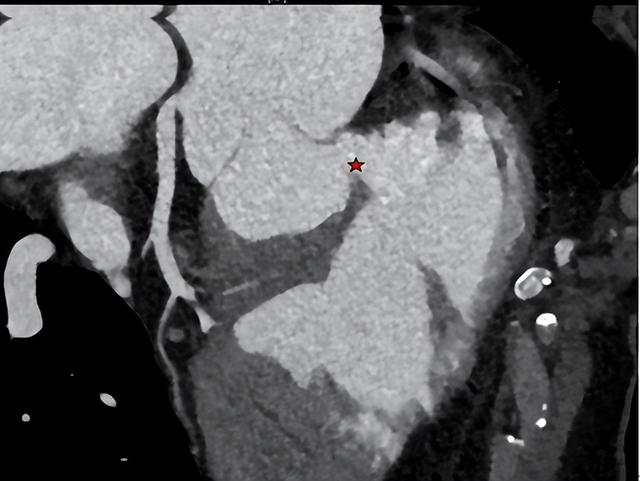

标红星处为室间隔残余缺损,直径约1.2cm

进一步心脏CT等检查显示,徐明的室间隔缺损直径达1.2cm,主动脉窦部瘤直径约6cm(正常约4cm),三尖瓣及肺动脉都有大量的反流。“这都是导致患者气喘、心衰的原因。”翁教授建议要趁患者年轻,积极加强抗心衰治疗,“一鼓作气纠正心脏存在的所有畸形,最大程度地恢复心脏正常的结构和功能,改善生活质量,保证满意的远期预后。”